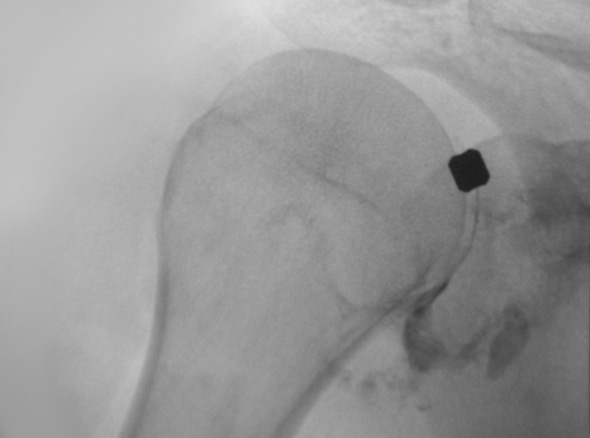

브리즈망 (관절수동술)

즉각적으로 통증을 완화해주고 어깨의 가동범위를 개선해주는 시술입니다.

주사 치료, 도수 치료 등을 하였으나 증상이 지속되는 경우

극심한 통증으로 스트레칭이 불가한 경우

정상 상태로 회복되는 걸리는 시간과 통증을 최소화 하고 싶은 경우